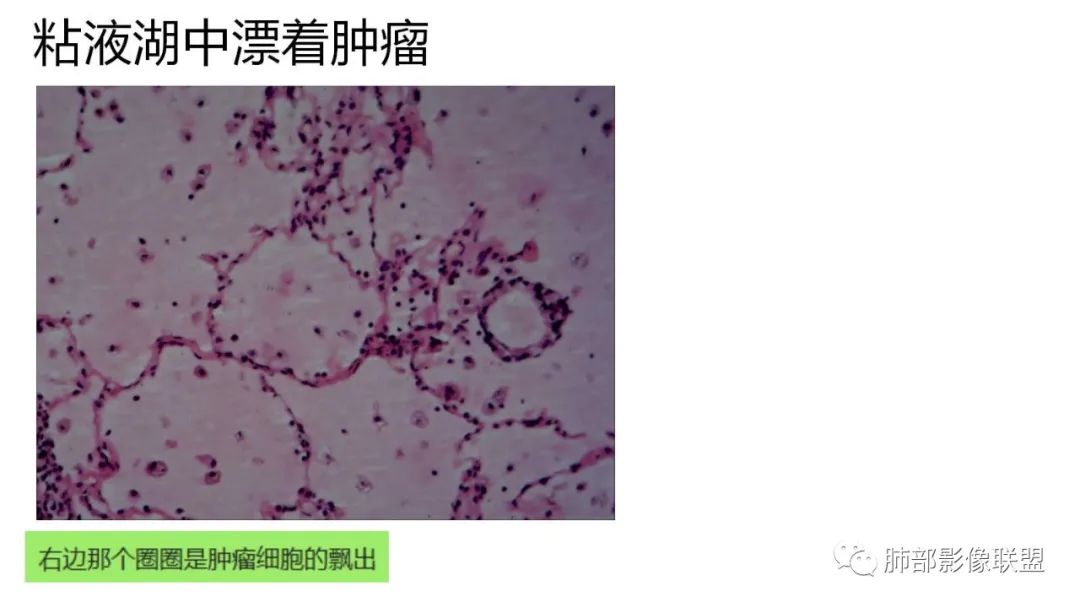

2、病灶常有一个主病灶,常位于下肺。后沿气道播散为多发病灶。

9.粘液腺癌的变化规律:结节缓慢发展而来,向周围播散形成斑片后可快速进展,有时支气管镜后或粘液排出后局部可形成好转的假象。病灶可沿肺泡和支气管播散。